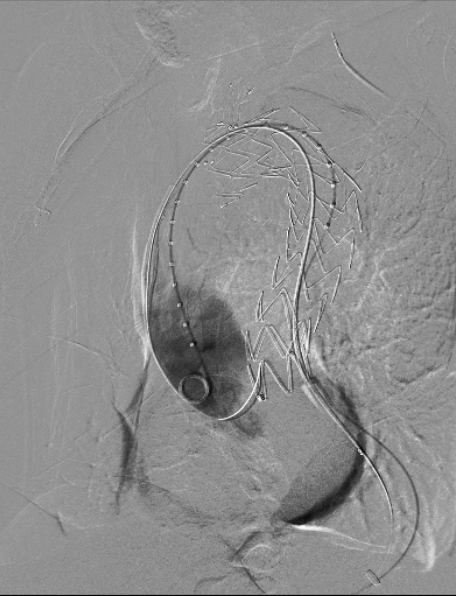

释放支架

经DSA造影确认支架位置准确后,快速释放主体支架,助手配合牵拉分支导丝释放分支支架。

治疗车怎么推「弓部重建直通车」鄂尔多斯市中心医院康巴什部介入科运用Castor®分支型支架联合预开窗技术治疗Stanford B型胸主动夹层_https://www.jmylbn.com_新闻资讯_第9张